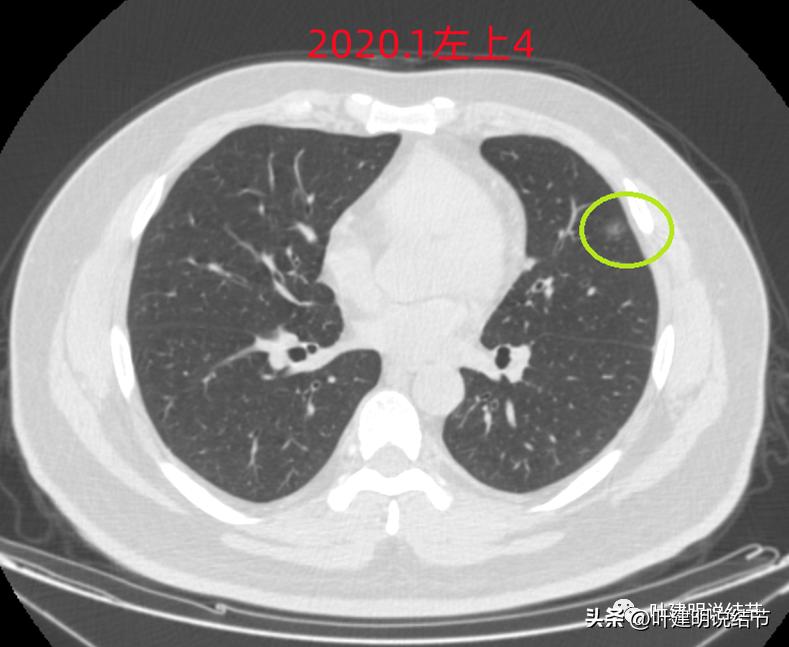

左上病灶4:舌段磨玻璃结节,边缘显力糊,整体轮廓较清,不典型增生可能性大点。